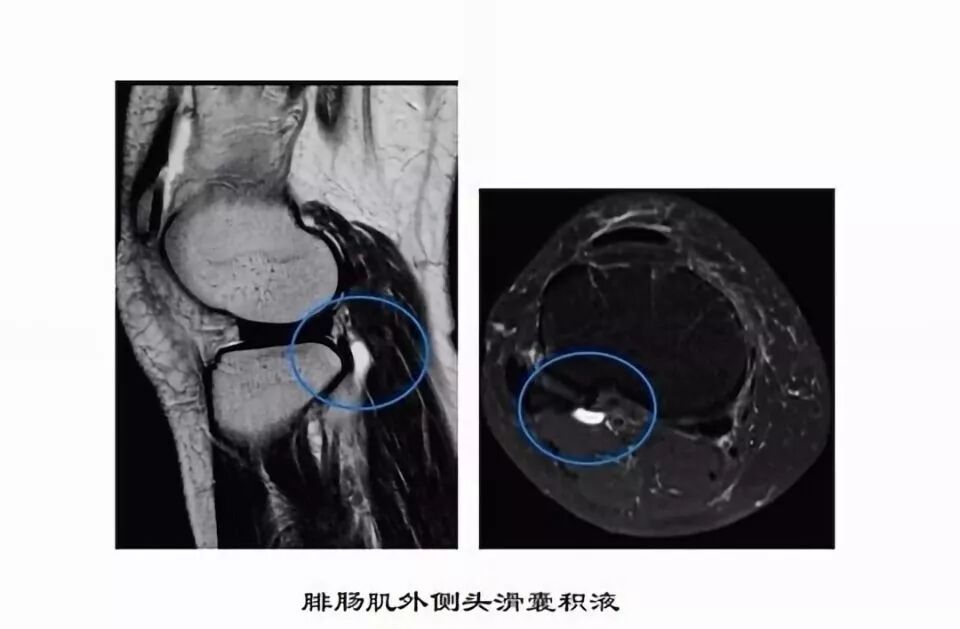

滑囊是关节囊外的囊性结构,可与关节囊相通,其作用是减少肌腱、骨和皮肤之间的摩擦。可以分为先天性滑囊和获得性滑囊。